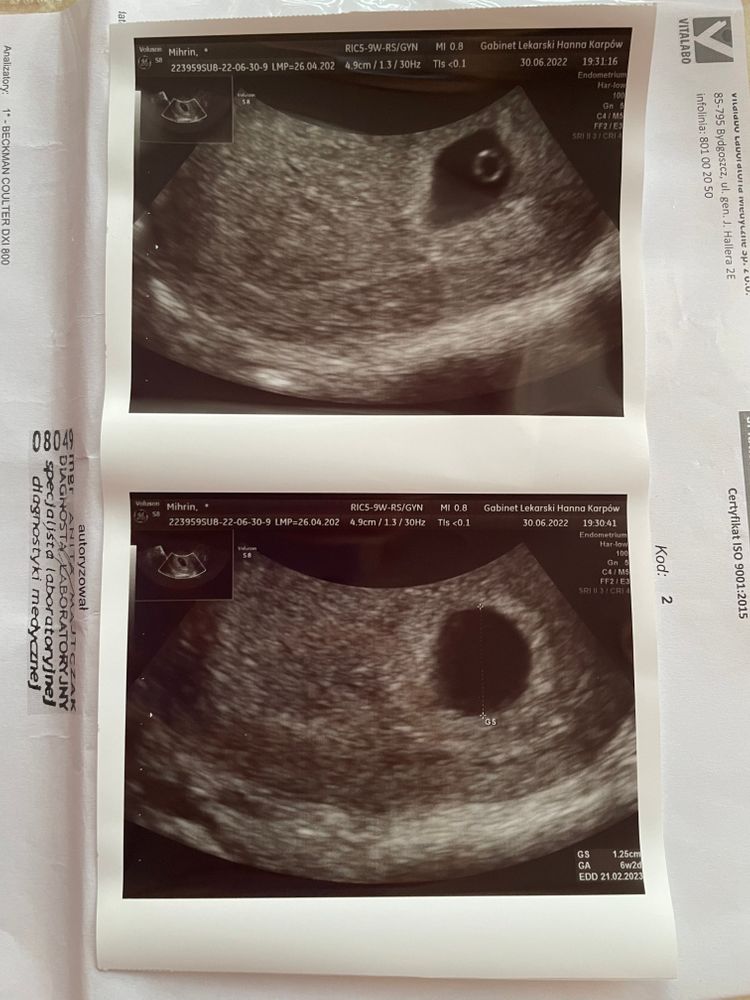

недели не эмбриона

4 5 недели не эмбриона 146 фото